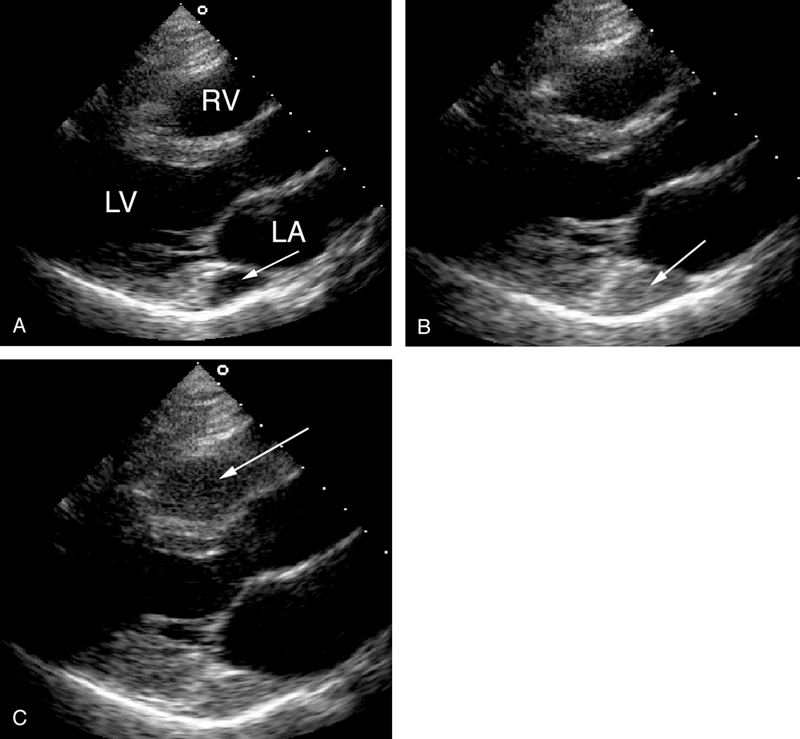

فحوصات تشخيصية لبعض امراض القلب والشرايين التاجية